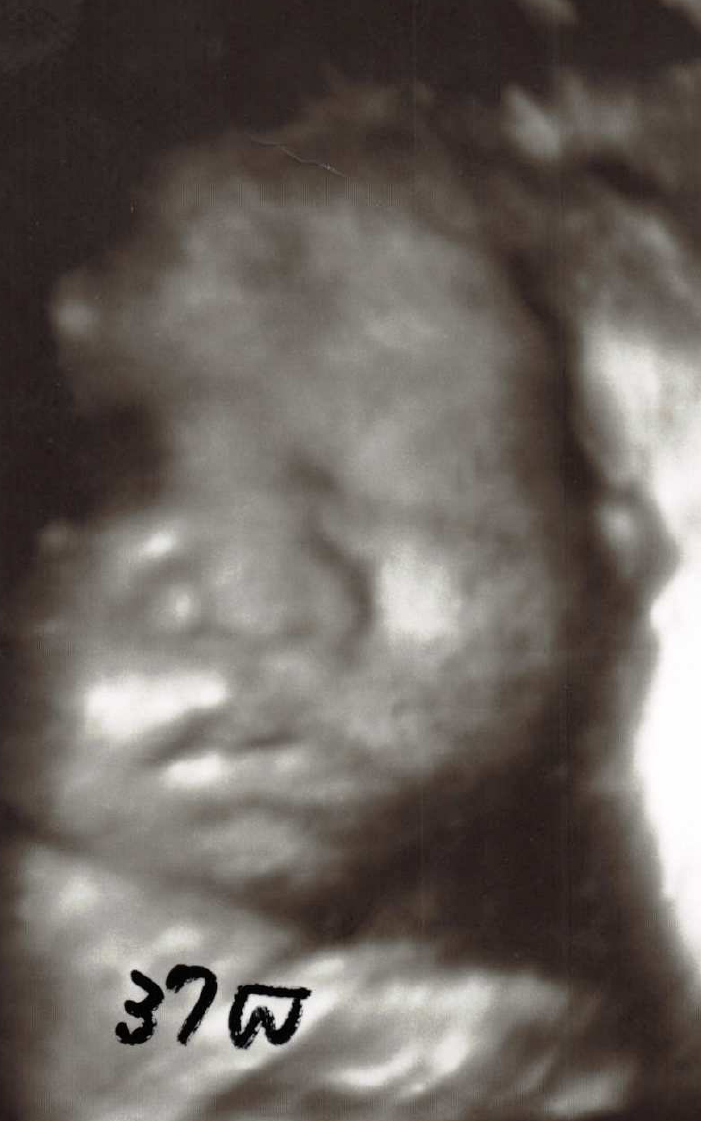

37週

7~8か月以降になると、特に、ふっくらした可愛い顔立ちが見えます。

3D,4Dでは特に赤ちゃんの顔が見えると嬉しいです。普段は

ウトウトと静かに寝ている感じですが、たまに

ニコッとしたり

機嫌の悪そうな顔をすることもあります。又たまに目を開けたり、眼をパチパチすることもあります。